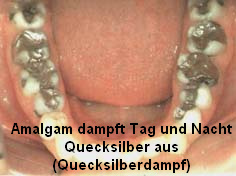

Amalgamgebiss mit Amalgam in Backenzähnen [1]

Amalgamgebiss

mit

Frontzähnen aus Amalgam [2] Amalgamgebiss

Amalgam dampft Tag und Nacht Quecksilber aus

(hochgiftiger Quecksilberdampf) [3]